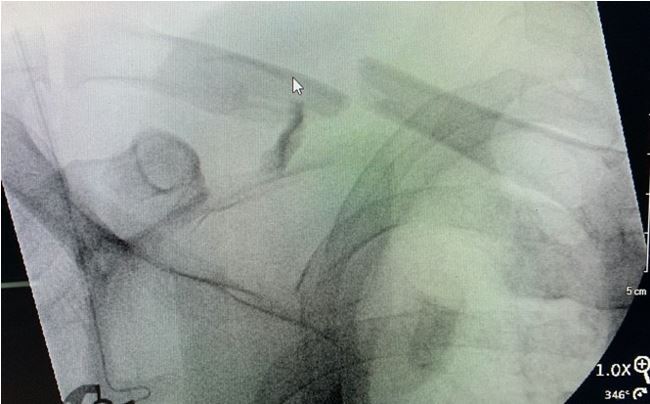

The patient was positioned on a radiolucent table in approximately 30 degrees of reverse Trendelenburg position with a bump under the scapula. The C-arm was positioned from the opposite side of the patient. The C-arm monitor and the D-MOD’s monitor were placed facing the surgeon near the patient’s contralateral hip. This positioning allowed full view of the clavicle exposure, fluoroscopic imaging, and drilling data (Figure 3). Exposure, reduction, and provisional fixation with a ten-hole curved small fragment plate was completed.